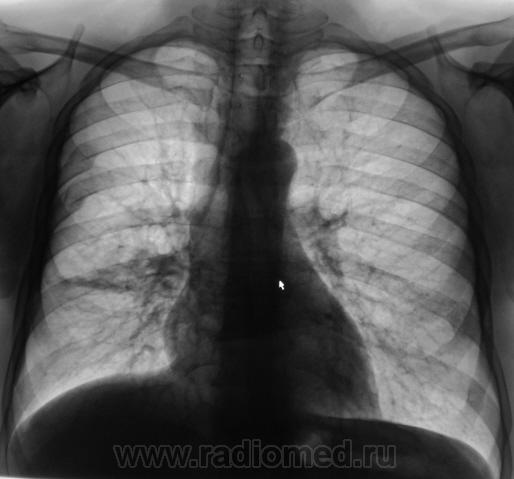

Пациент направлен терапевтом в рентгеновский кабинет с диагнозом - "Правостороняя пневмония".

Пациент направлен терапевтом в рентгеновский кабинет с диагнозом - "Правостороняя пневмония". Произведено стандартное исследование.

Пока картина слвной инфильтрации в 6 сегменте, но настораживает сгущение рисунка в нем, нужно повторно исследовать после лечения... Может прорезаться более грозая болезнь.

Скорее всего ателктаз 6 сегмента. Он явно объемно уменьшен, да и на качественной боковой можно найти ампутацию бронха, а на прямой томо - не все в поряде с корнем. Валентин Львович, доброе утро! Вы будете не собой, если не выложите серию боковых томограмм.

Здравствуйте! Клиники инфаркта легкого нет?

Вообще-то, объёмного уменьшения нижней доли справа нет ( все сосуды на месте)-вероятно, это не ателектаз.